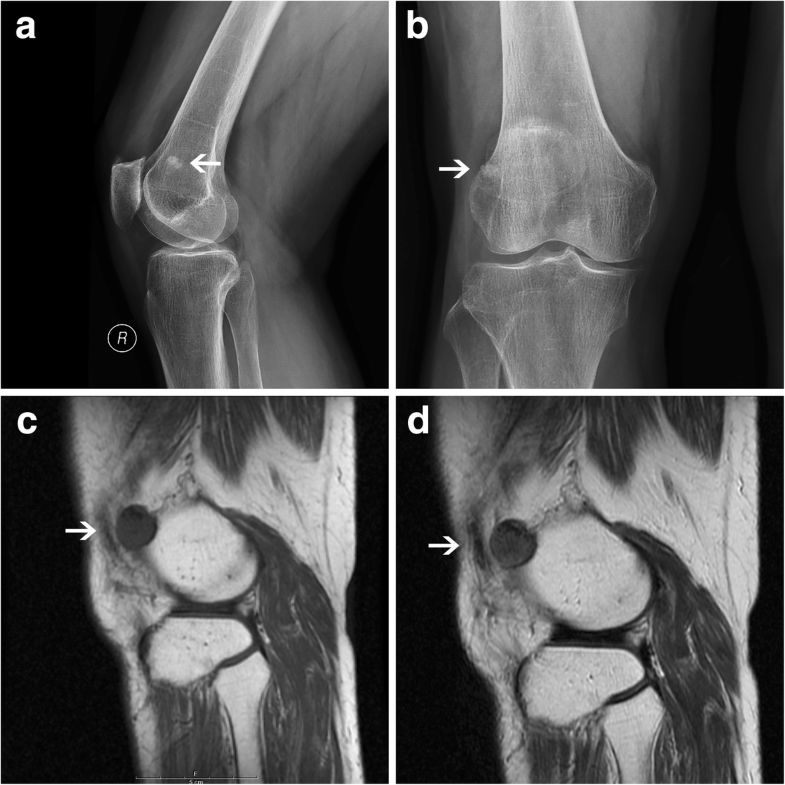

The diagnosis and arthroscopic treatment of angioleiomyoma presenting Knee Injuries Case Report blunt traumatic injury to the popliteal artery is uncommon and typically requires significant force applied to the. maximum outcome with minimal resources: the patient undergoes an mri scan to check for knee injuries. The study shows a grade 3 osteoarthritis that is. the prevalence of paediatric knee injuries is increasing due to higher participation in competitive. Knee Injuries Case Report.